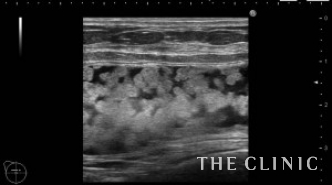

1年前に他院にて脂肪注入による豊胸を受けられた方です。2ヵ月程前にしこりに気付き、除去して欲しいとのことで当院へご来院されました。エコー所見です。両側とも乳腺下にあり、右10㎝、左5㎝の被膜に包まれた混合性(充実成分+嚢胞成分)のしこりです。この他に、1㎝のオイルシストが左に確認出来ました。